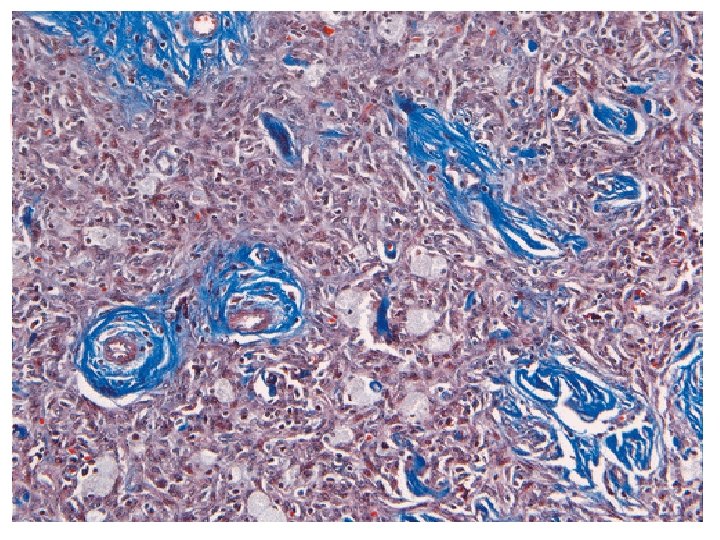

MASSON’S TRICHROME STAIN n n n Components : phosphotungstic acid, methyl blue, acid fuschin in glacial acetic acid and distilled water Uses : to stain collagen fibres and muscle tissue Color : collagen-blue/green cytoplasm, muscles, RBCs-red nuclei-blue/black

Acid fuchsin 586 Methyl blue 800 Acid fuchsin RBCs Muscle Collagen Methyl blue Collagen Results : Nuclei blue / black Collagen blue (methyl blue) Muscle & RBCs Red (acid fuchsin)